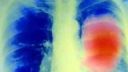

Pľúca fajčiara vs. pľúca nefajčiaraAutor: jozef24096 655 videní

Čo vám zostane v pľúcach po 400 cigaretách?Autor: sssr119 653 videní